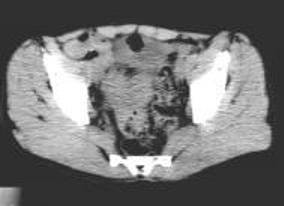

病历摘要:男,54岁病史:间歇性肉眼血尿伴下腹部隐痛7月余。为全程血尿,浓茶色,并有尿频尿急尿痛。当地医院曾造影检查示“膀胱结石”,入院前3天当地医院检查示“膀胱肿瘤”体查:心肺腹无明显阳性体征,双肾区无叩痛,双输尿管行程无压痛点,膀胱区未见肿胀、隆起实验室检查:尿常规:淡黄色,混浊,潜血大量,镜检白细胞370/μl(↑)